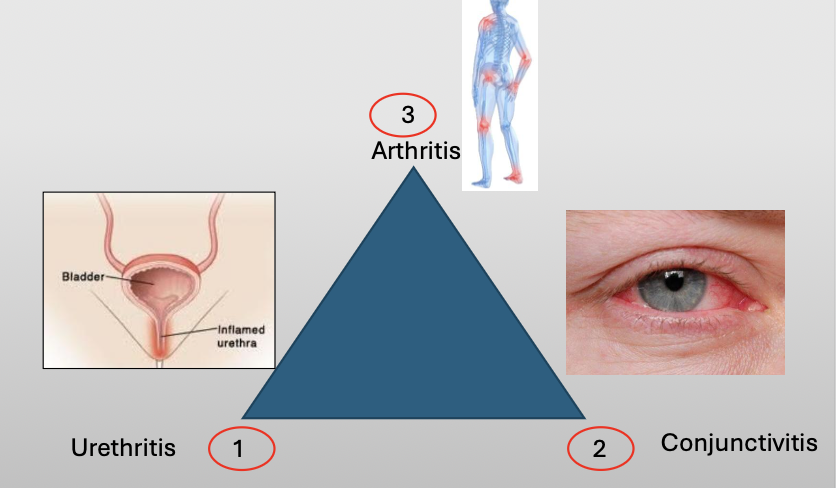

What is another name for reactive arthritis

Reiter Syndrome

What is Reiter Syndrome?

A chronic disease that classically compromises a triad of three featuers:

Urethritis

Conjunctivitis

Arthritis

What is the cause of Reiter Syndrome?

Unknown, 10% have HLA-B27

Oral lesions are 20% (nonspecific)

NSAID/AB if infection/steroids

What demographic does Reiter Syndrome show up in?

M:F (9:1)